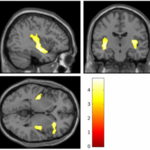

Brains Of Teenage Girls Who Engage In Cutting Are Similar To Those With Borderline Personality Disorder

A pilot study in Development and Psychopathology concluded that teenage girls who engage in self-harm like cutting often have brain features like adults with borderline personality disorder. Often is relative, since this was only 40 individuals. Cutting and other forms of self-harm are warning signs for suicide, which data from the Centers for Disease Control and Prevention say increased 300 percent among 10- to 14-year-old girls from 1999 to 2014, according to data from the Centers for Disease Control and Prevention. During that same time, along with a 53 percent increase in suicide in older…